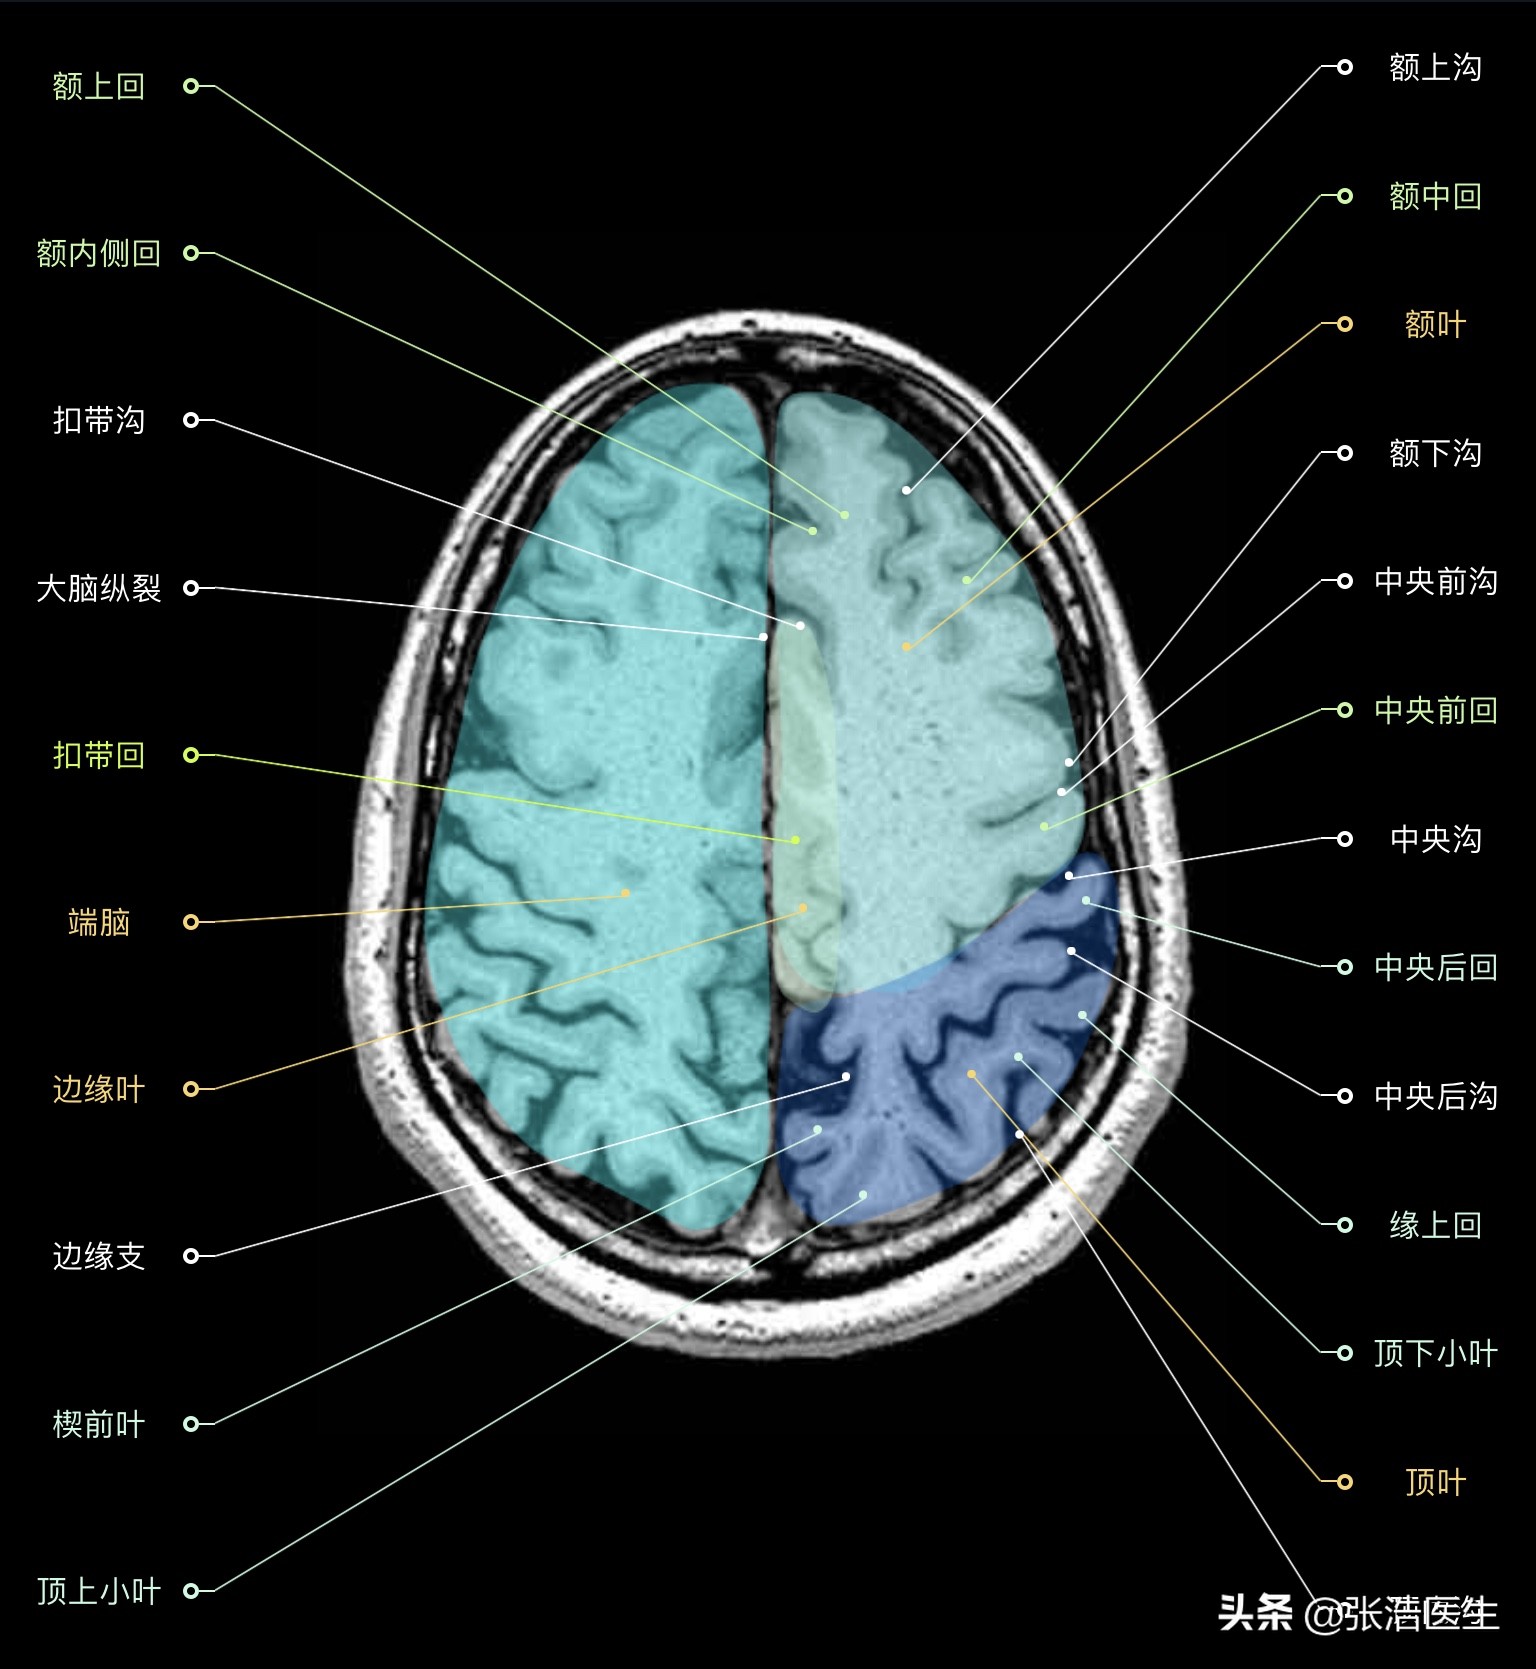

颅脑MRI横断面高清解剖图谱(图层3)